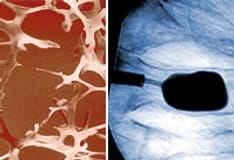

Radiologic features include widening of the epiphysial plate, cupping, and deformities in the shaft of long bones. Of note, radiographs of the costochondral junction are not useful in the diagnosis of rickets. The healing process is characterized by broadened bands of increased density.

Syndrome resembling osteogenesis imperfecta (SROI) with mineralization defect is clinically indistinguishable from moderate to severe osteogenesis imperfecta. [10] (This rare form, in fact, has been termed type VI osteogenesis imperfecta.) It can only be diagnosed with bone biopsy, in which a mineralization defect that affects the bone matrix and sparing growth cartilage are evident. These patients have neither dentinogenesis imperfecta nor Wormian bones. Despite the histologic mineralization defect, no radiologic signs of growth plate involvement are seen.

Radiograph in a 4-year-old girl with rickets depicts bowing of the legs caused by loading.

Findings in patients with rickets.